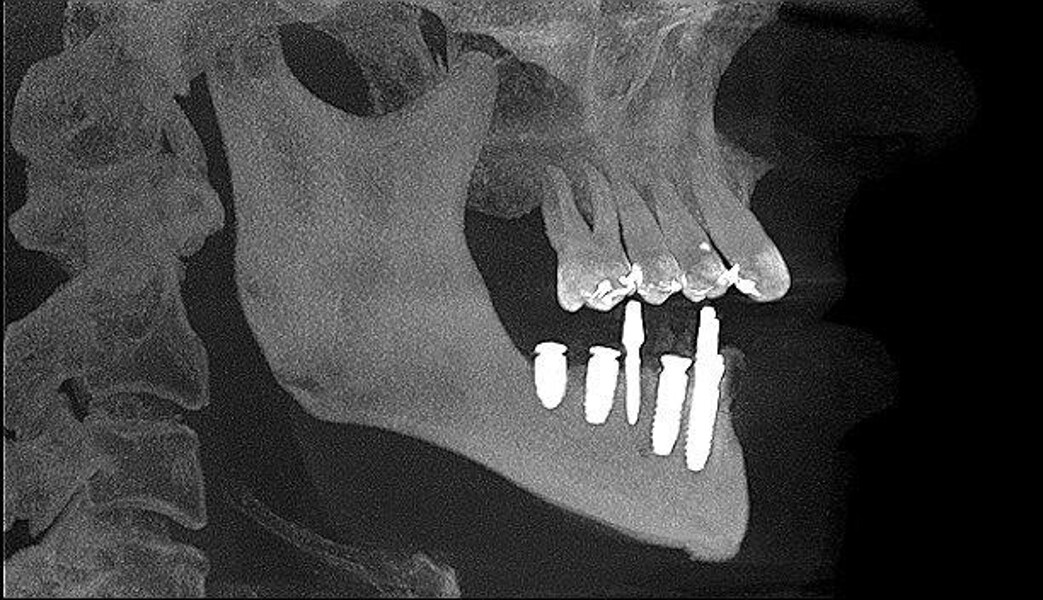

Implantacja z wykorzystaniem szablonu nawigacyjnego 3D